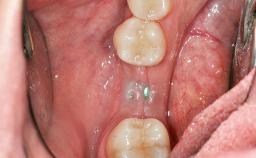

Soft-Tissue Volume Augmentation Using a Connective-Tissue Graft Harvested from the Maxillary Tuberosity

| Jaw | Mandible |

| Area | Posterior |

| # of Teeth | 1 |

| # of Implants | 1 |